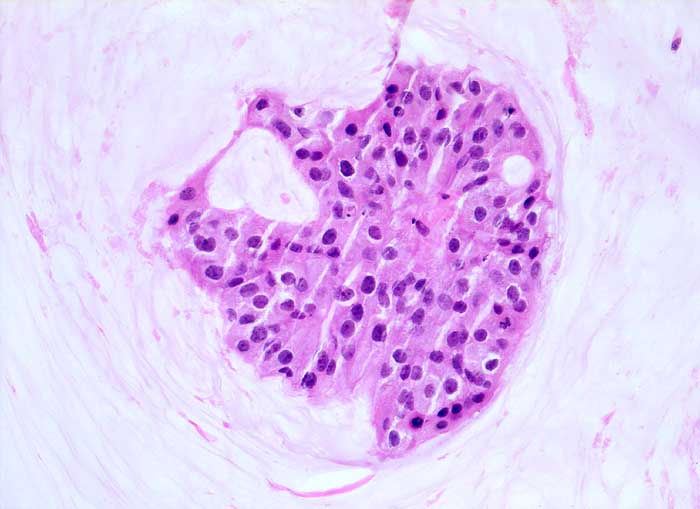

Einleitung

Homogene oder schlierenförmige extrazelluläre Schleimmassen mit Inseln von Tumorzellen mit geringen Kernatypien sind pathognomonisch für das muzinöse Mammakarzinom. Die Zellzahl ist meist nicht sehr hoch. Die Zellen liegen einzeln oder in kleinen kugeligen oder pseudopapillären Verbänden. Der Schleim erscheint in der Pap Färbung blau-grau bis rötlich. Siegelringkarzinome zeigen grössere intrazytoplasmatische Schleimvakuolen.

Unten werden zwei Beispiele von typischen muzinösen Karzinomen gezeigt.